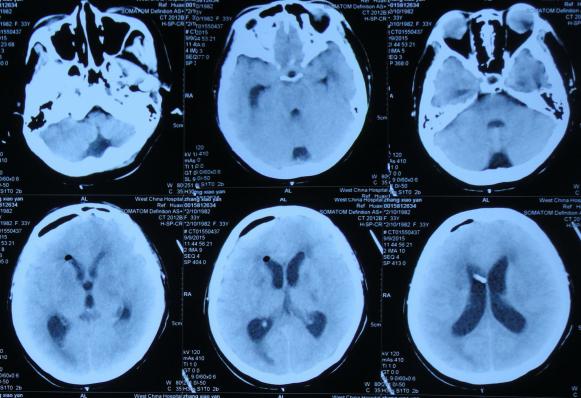

经头孢哌酮舒巴坦抗感染治疗1周后即2015年8月9日,仍间断头痛,发热有下降,但仍反复,但患者意识反变差,表情也变淡漠,查头部CT(图-2)。

图-2:2015年8月9日头部CT

第1家医院治疗13天后即2015年8月16日,查头CT:双侧侧脑室,三脑室及四脑室扩张(图-4),且给予腰穿检查,提示颅压高(脑脊液检查结果不详),给予相关对症治疗。

图-4:2015年8月16日头部CT

第1家医院治疗16天后即2015年8月19日,间断头痛,腰穿颅内压仍高,查头部CT示脑室进一步扩张(图-5)。

图-5:2015年8月19日头部CT